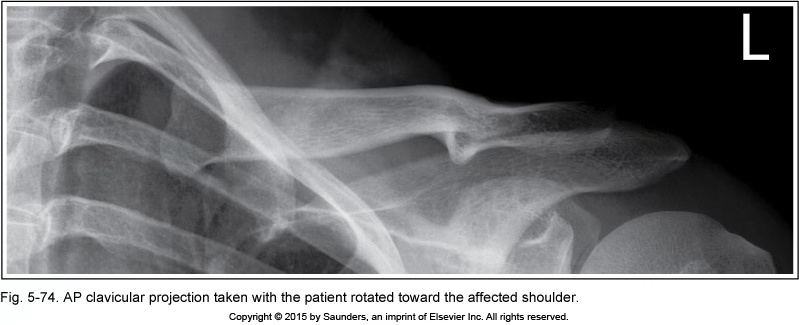

AP clavicle

Pt rotated into LPO (affected shoulder)

open space between vertebral column and clavicle

clavicle shortened